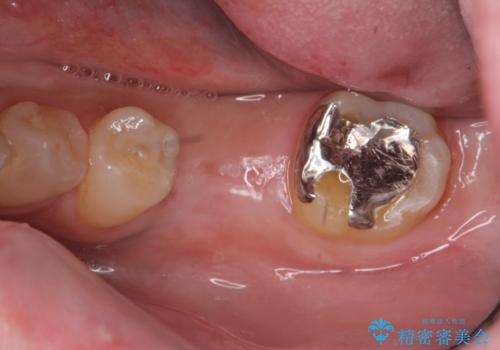

- 強く噛みしめる癖や歯ぎしりにより歯が割れてしまい、抜歯後のインプラント治療を求めて来院されました。

歯に大きな力がかかると、特に大きな銀歯の入った歯や神経治療をしたことのある歯は割れてしまい抜歯を余儀なくされる可能性が高まります。